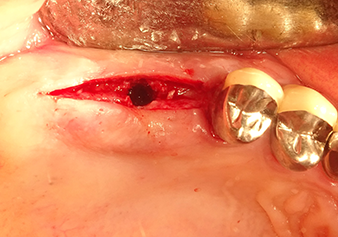

La membrana di Schneider viene allungata di 1,5-2 mm sopra l'accesso del tessuto osseo

Fig.4: Controllo intermedio: l'altezza ossea sopra il seno mascellare è di ca. 4 mm palatale e buccale; la membrana di Schneider viene allungata di 1,5-2 mm sopra l'accesso del tessuto osseo.